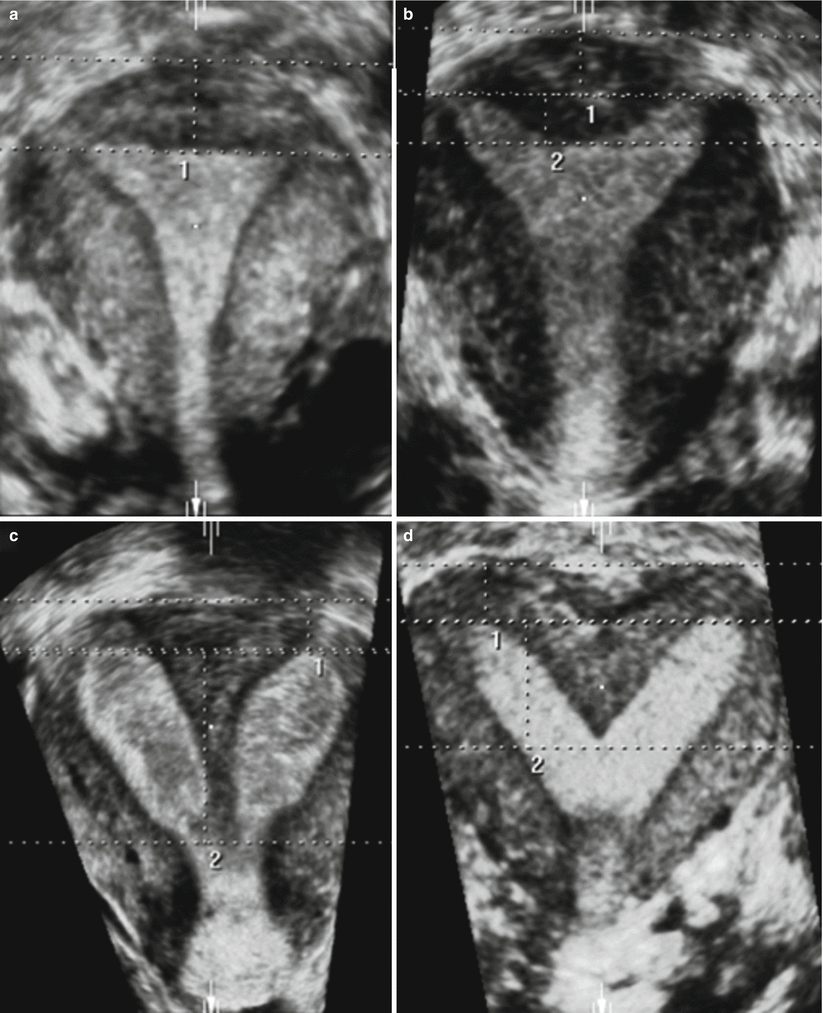

Current treatments include hysterectomy, myomectomy, uterine artery embolization, magnetic resonance imaging (MRI)–guided focused ultrasound treatment, medical treatment based on hormone therapy (eg, progestin or gonadotropinreleasing hormone agonists), and endometrial ablation for women who are finished with childbearing The initial step in evaluating a woman with Sessile subserosal fibroids A little sessile subserosal fibroid on the superior face of the uterus (arrow) with heterogeneous low signal intensity on sagittal T2weighted image (TR 4,500 ms, TE 90 ms) (a) and with low signal enhancement on contrastenhanced fatsuppressed T1weighted image (TR 4 ms, TE 2 ms) (b)Another woman (c and d) with a sessile subserosal Transvaginal ultrasound shows an enlarged uterus with a finely heterogeneous echo pattern (Courtesy of Sherelle LaiferNarin, MD) FIGURE 1912 Two cases of

–808 807 Sakhel and Abuhamad—Sonography of Adenomyosis Figure 5 Measurement of the length of a posterior uterine wall that is greater than that of the anterior wall (calipers) and has a heterogeneous myometrial echo texture Figure 4 Heterogeneous myometrium is more prevalent and consistent indicator for the diagnosis of adenomyosis by ultrasound Though enlarged uterus is almost invariably present in cases of adenomyosis (93%), yet it is totally nonspecific and is also present in multiparous females (see Figure 3, Figure 4) Download Download fullsize image;For postmenopausal women, transvaginal ultrasound evalua

Muscular hyperplasia and hypertrophy cause focal or diffuse myometrial thickening and globular uterine enlargement, often with thin "venetian blind" shadows The combination of these findings results in a heterogeneous myometrium, with blurring of the endometrial borderUnicornuate uterus is presented Abdominal and pelvic ultrasound revealed ahypertrophied right kidney measuring 130 cm, anormal right ovary, and absent left kidney and ovary Computerized tomography of the abdomen and pelvis confirmed absence of the left kidney and ovary and revealed aunicornuate uterus with absent left hornImaging of leiomyomas and their variants allows classification by location in the uterus and pretreatment planning Ultrasound is the firstline imaging modality because it is a costeffective portable realtime examination that provides good anatomic detail without radiation

Adenomyosis A Sonographic Diagnosis Radiographics